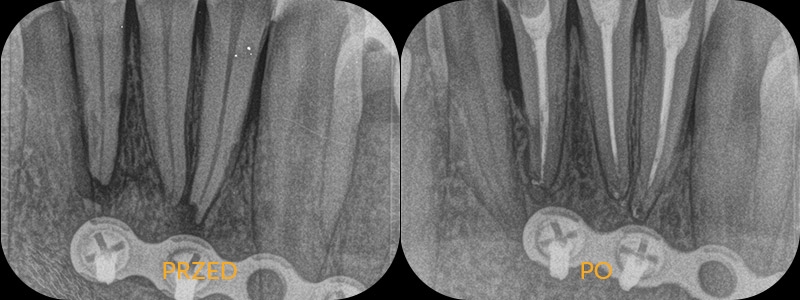

Pacjent leczony poza naszą kliniką zgłasza się z bólem. Zdjęcie wykazuje zmiany zapalne okołokorzeniowe, a także pozostawione w kanale złamane narzędzie (pilnik), które uniemożliwia jego opracowanie. Tylko w powiększeniu mikroskopu lekarz jest w stanie usunąć przeszkodę i opracować kanał do końca. Nasza endodontka przystępuje do pracy, usuwając najpierw narzędzie, potem wykonując powtórne leczenie kanałowe. Kontrolne zdjęcie wykazuje prawidłowe wypełnienie kanałów, a także gojenie zmiany zapalnej.